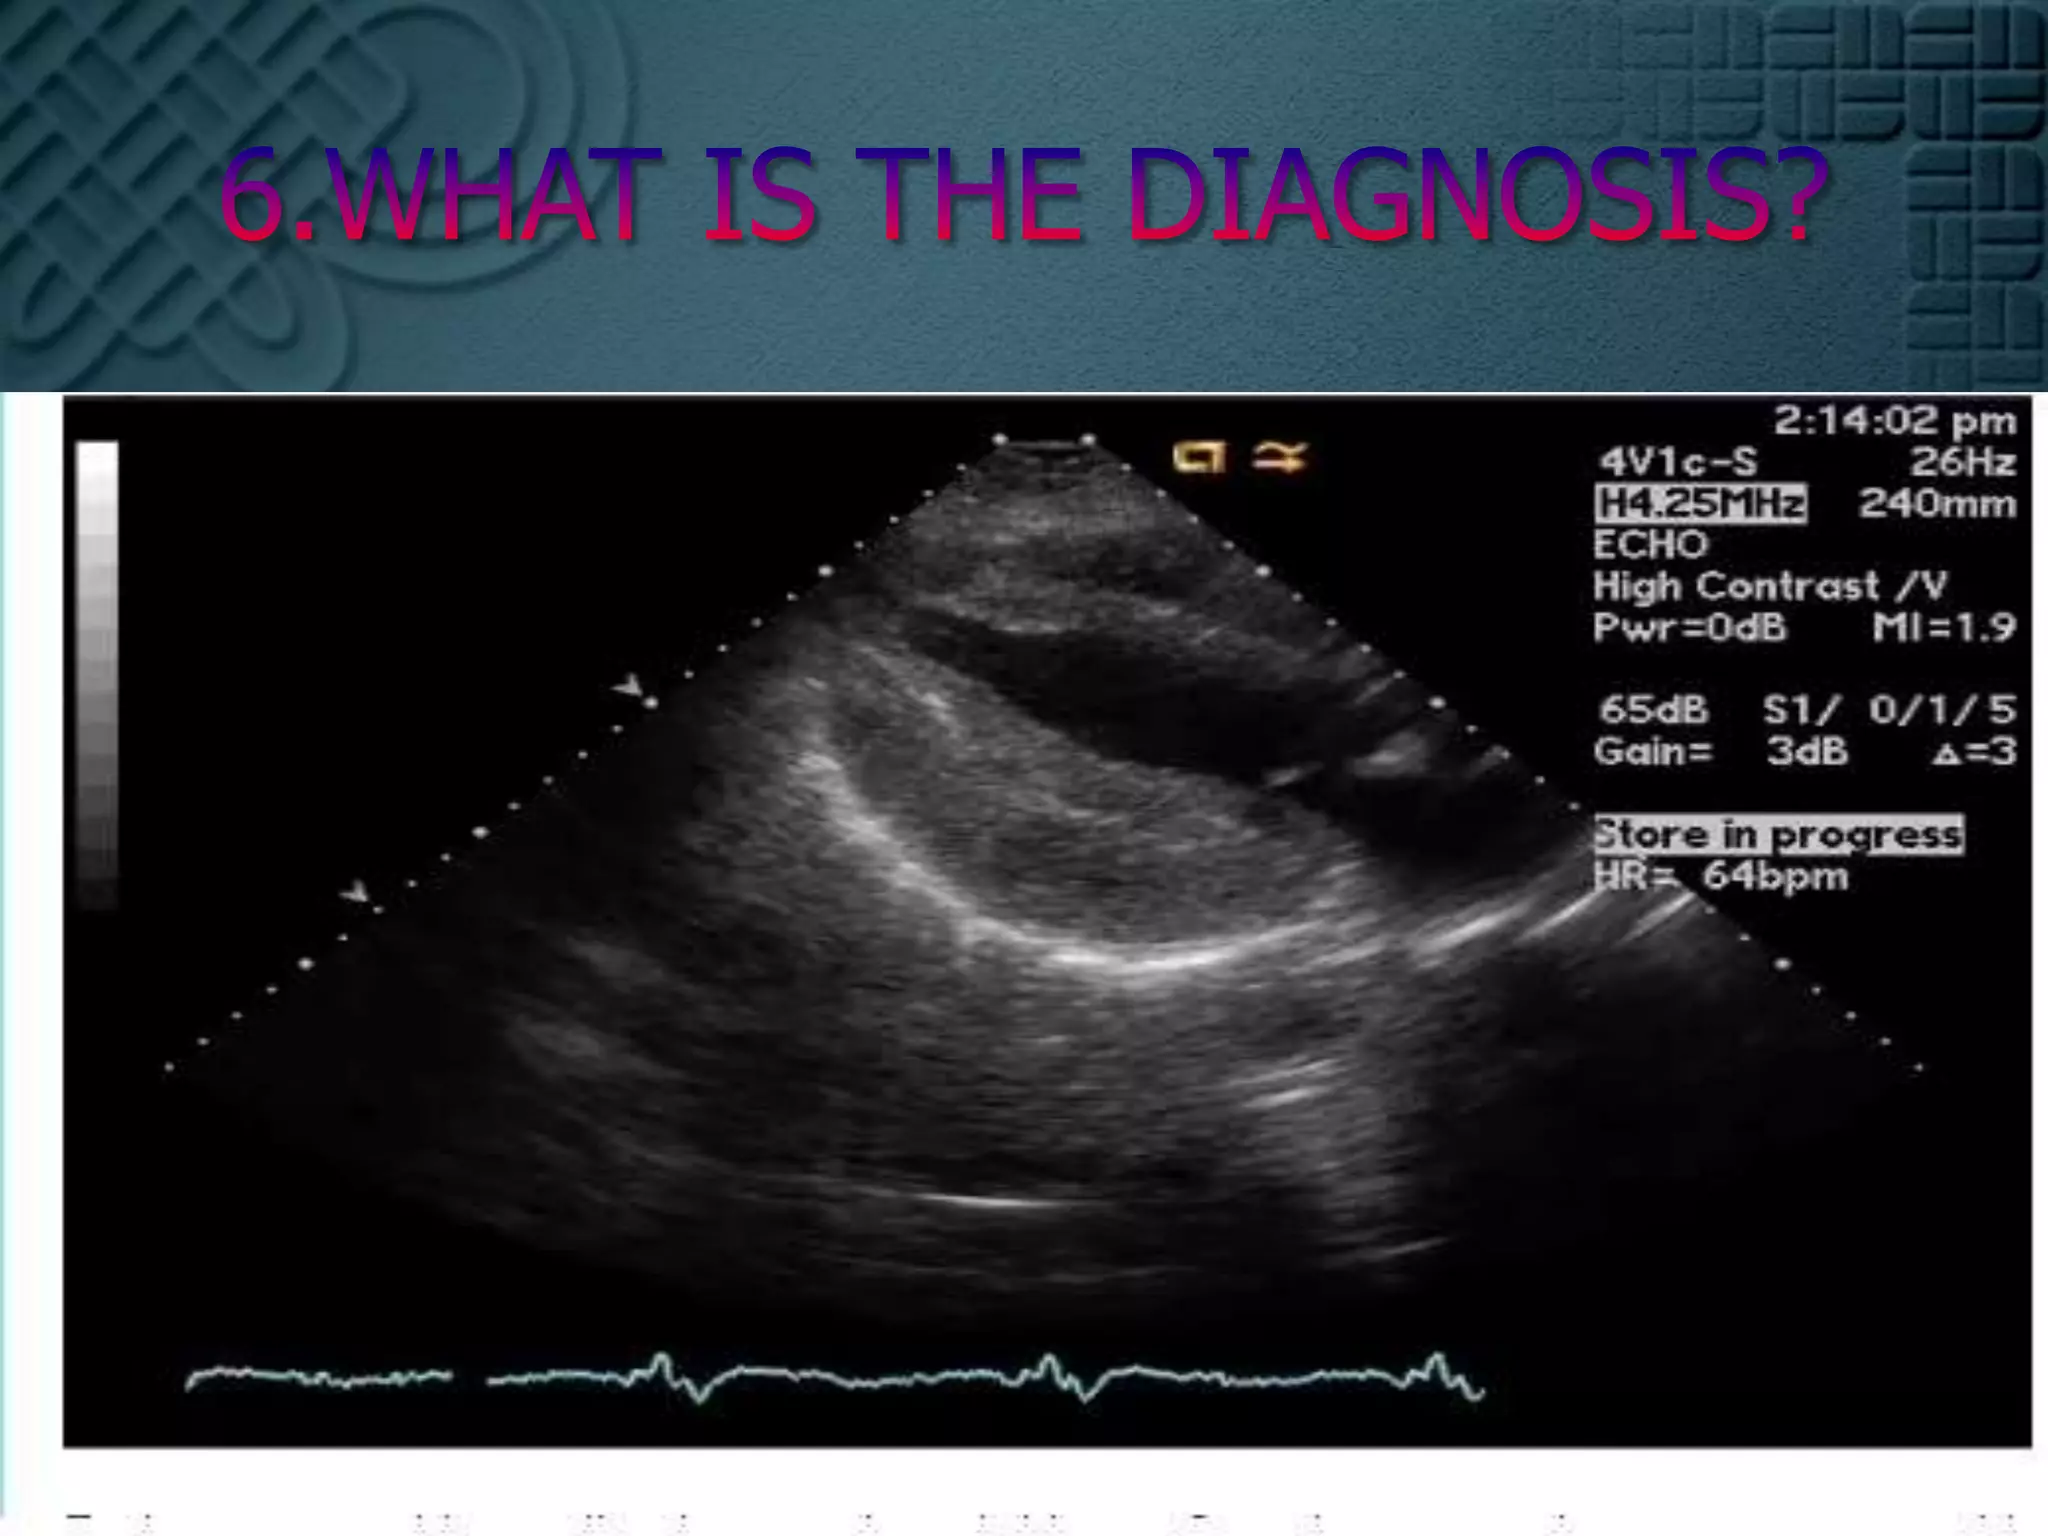

6.This 74 yo male had just returned to his unit bed after successful PTCA of tight lesions of the first diagonal and obtuse marginal coronaries. He complained of chest pain. This ECG was recorded. The previous is below.

6.WHAT IS THE DIAGNOSIS?

6.This 74 yomale had just returned to his unit bed after successful PTCA of tight lesions of the first diagonal and obtuse marginal coronaries. He complained of chest pain. This ECG was recorded. The previous is below.

6.WHAT IS THEDIAGNOSIS?